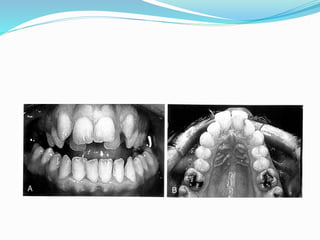

 Posterior crossbite

 Crowding

 Hourglass arch

 Deep palate

 Dental or skeletal